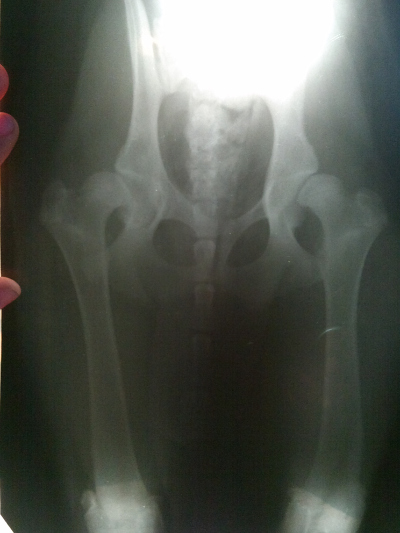

Рентгенограммы должны выполняться под седалгией или под наркозом, чтобы обеспечить нужное положение сустава. Стандартный рентгенографический снимок делается, когда собака находится в дорсальном положении с вытянутыми параллельно задними конечностями, колени повернуты так, чтобы коленная чашечка находилась в центре блоковой борозды и симметрично расположенным тазом. Вентродорсальный вид должен включать два поясничных позвонка и оба колена. Тяжесть клинических симптомов не соотвествует тяжести рентгенографических изменений. Рентгенографическая съемка под нагрузкой поможет количественно оценить степень слабости сустава.

Рентгенограммы (т. Е. Рентгеновские снимки) необходимы для оценки костей тазобедренного сустава и обычно требуют седативных средств как для обеспечения взаимодействия кошки, так и для минимизации боли в суставе, пораженном артритом.

Стандартный вид: кошка лежит на спине, а ее задние лапы вытянуты прямо. Этот вид похож на оценочную рентгенограмму, необходимую для подтверждения OFA степени дисплазии бедра. (OFA классифицирует бедра по семи различным категориям: отличное, хорошее, удовлетворительное, пограничное, легкое, умеренное или тяжелое.) Для сертификации PennHIP выполняются дополнительные обзоры, которые учитывают измерения дряблости суставов, а также конформации тазобедренных суставов.

Рентгенограммы таза взрослой собаки с нормальными тазобедренными суставами, сравните их с приведенной ниже собакой с дисплазией тазобедренного сустава

Пожилая кошка с дисплазией тазобедренного сустава

Белыми стрелками обозначено большое количество стула в толстой кишке указанной кошки с дисплазией тазобедренного сустава. Этой кошке больно сидеть на корточках, чтобы опорожнить кишечник, в результате чего у нее сильно запор.